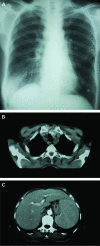

Unexpected finding on staging bone marrow aspirate for Hodgkin's lymphoma